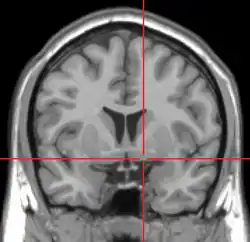

![]() Coronal MRI slice with cross-hairs indicating location of the substantia innominata | |

The substantia innominata, also innominate substance or substantia innominata of Meynert (Latin for unnamed substance), is a series of layers in the human brain consisting partly of gray and partly of white matter, which lies below the anterior part of the thalamus and lentiform nucleus. It is included as part of the anterior perforated substance (as it appears to be perforated by many holes which are actually blood vessels). It is part of the basal forebrain structures and includes the nucleus basalis. A portion of the substantia innominata, below the globus pallidus is considered as part of the extended amygdala.[1]